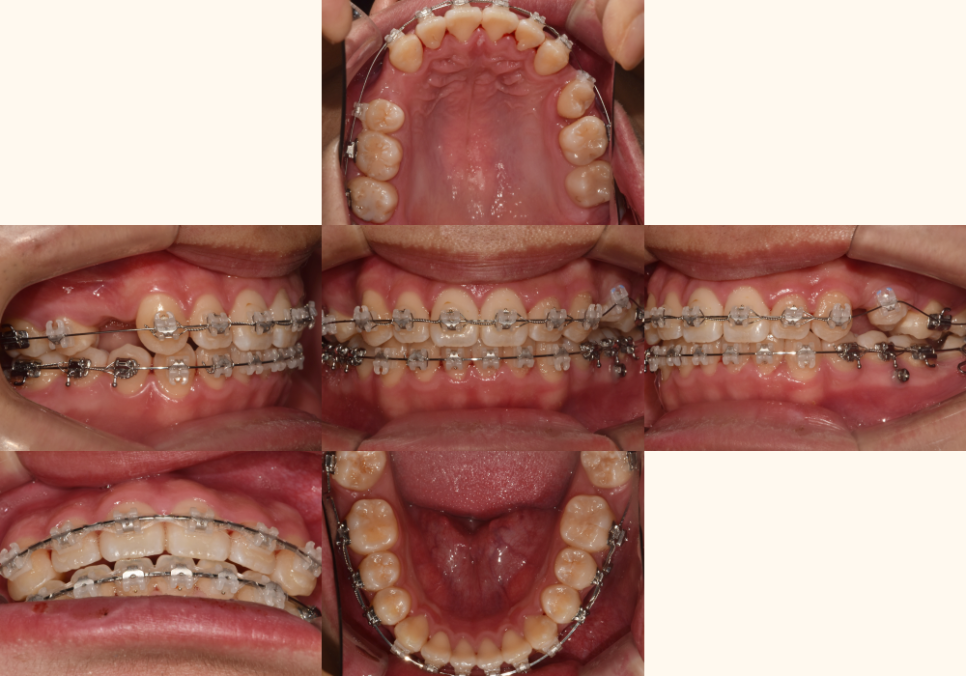

[사랑니 이동]

24.05.01

손상된 어금니 대신

건강한 사랑니를 앞쪽으로 이동시켜

어금니 역할을 하도록 하는 과정입니다.

이는 임플란트나 브릿지 없이도

자연치만으로

문제를 해결할 수 있습니다.

24.09.05//25.01.10

동시에 절단연 교합과 정중선 문제도

전체적인 치아 이동 과정에서 같이 개선됩니다.

치아들이 올바른 위치로 이동하면서

자연스럽게 교합 관계도 정상화되죠.